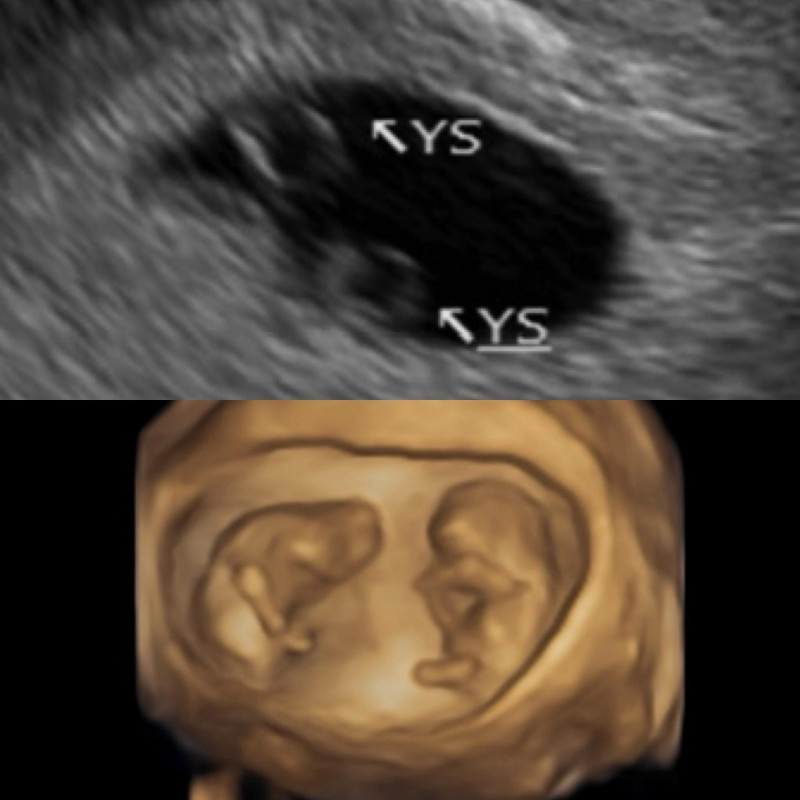

5410076_1 鄭家純曬超音波照,自然受孕「同卵雙胞胎」。(翻攝自臉書)

她回憶在醫院產檢時,超音波影像中一閃而過第二個圈圈,超音波師驚呼:「恭喜妳,是雙胞胎~」,讓她既驚訝又擔憂,因為同卵雙胞胎風險較高。直到6週時聽到心跳,她當場淚崩:「聽到的瞬間眼淚就掉下來,因為上次沒有聽到。」

鄭家純原本已與醫院約好過年後進行冷凍胚胎植入檢查,沒想到兩次都是「約好回診就立刻自然懷孕」。她特別感謝醫師在心理與醫學上的支撐,讓她能平穩度過脆弱的孕早期。鄭家純也分享了10週時的超音波照,兩個寶寶頭一上一下,模樣神似太極圖形。目前已滿12週的她,正以平靜的心接受身體變化。